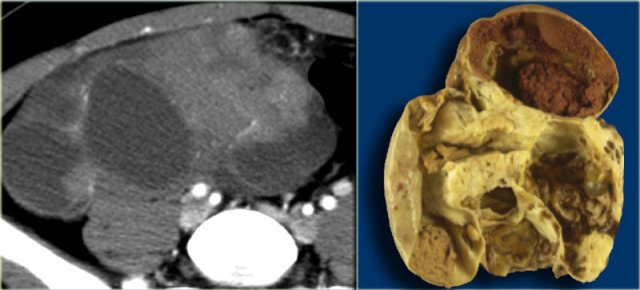

Classic low attenuation consistent with fat in a right sided cystic teratoma at CT.

A very common benign ovarian lesion that may appear cystic is a mature cystic teratoma, also called dermoid cyst.

Mature in this context means benign, as opposed to the immature, malignant teratoma.

Benign cystic teratomas typically occur in young women of child-bearing age.

At imaging they are usually unilocular (up to 90%) but can be multilocular, and are bilateral in ~15%.

Up to 60% may contain calcifications.

The cystic component is fluid fat, produced by sebaceous glands in cyst lining.

The presence of fat is diagnostic.

The characteristic ultrasound appearance is that of a cystic mass, with a hyperechoic solid mural nodule, which is called a Rokitansky nodule or dermoid plug (figure).